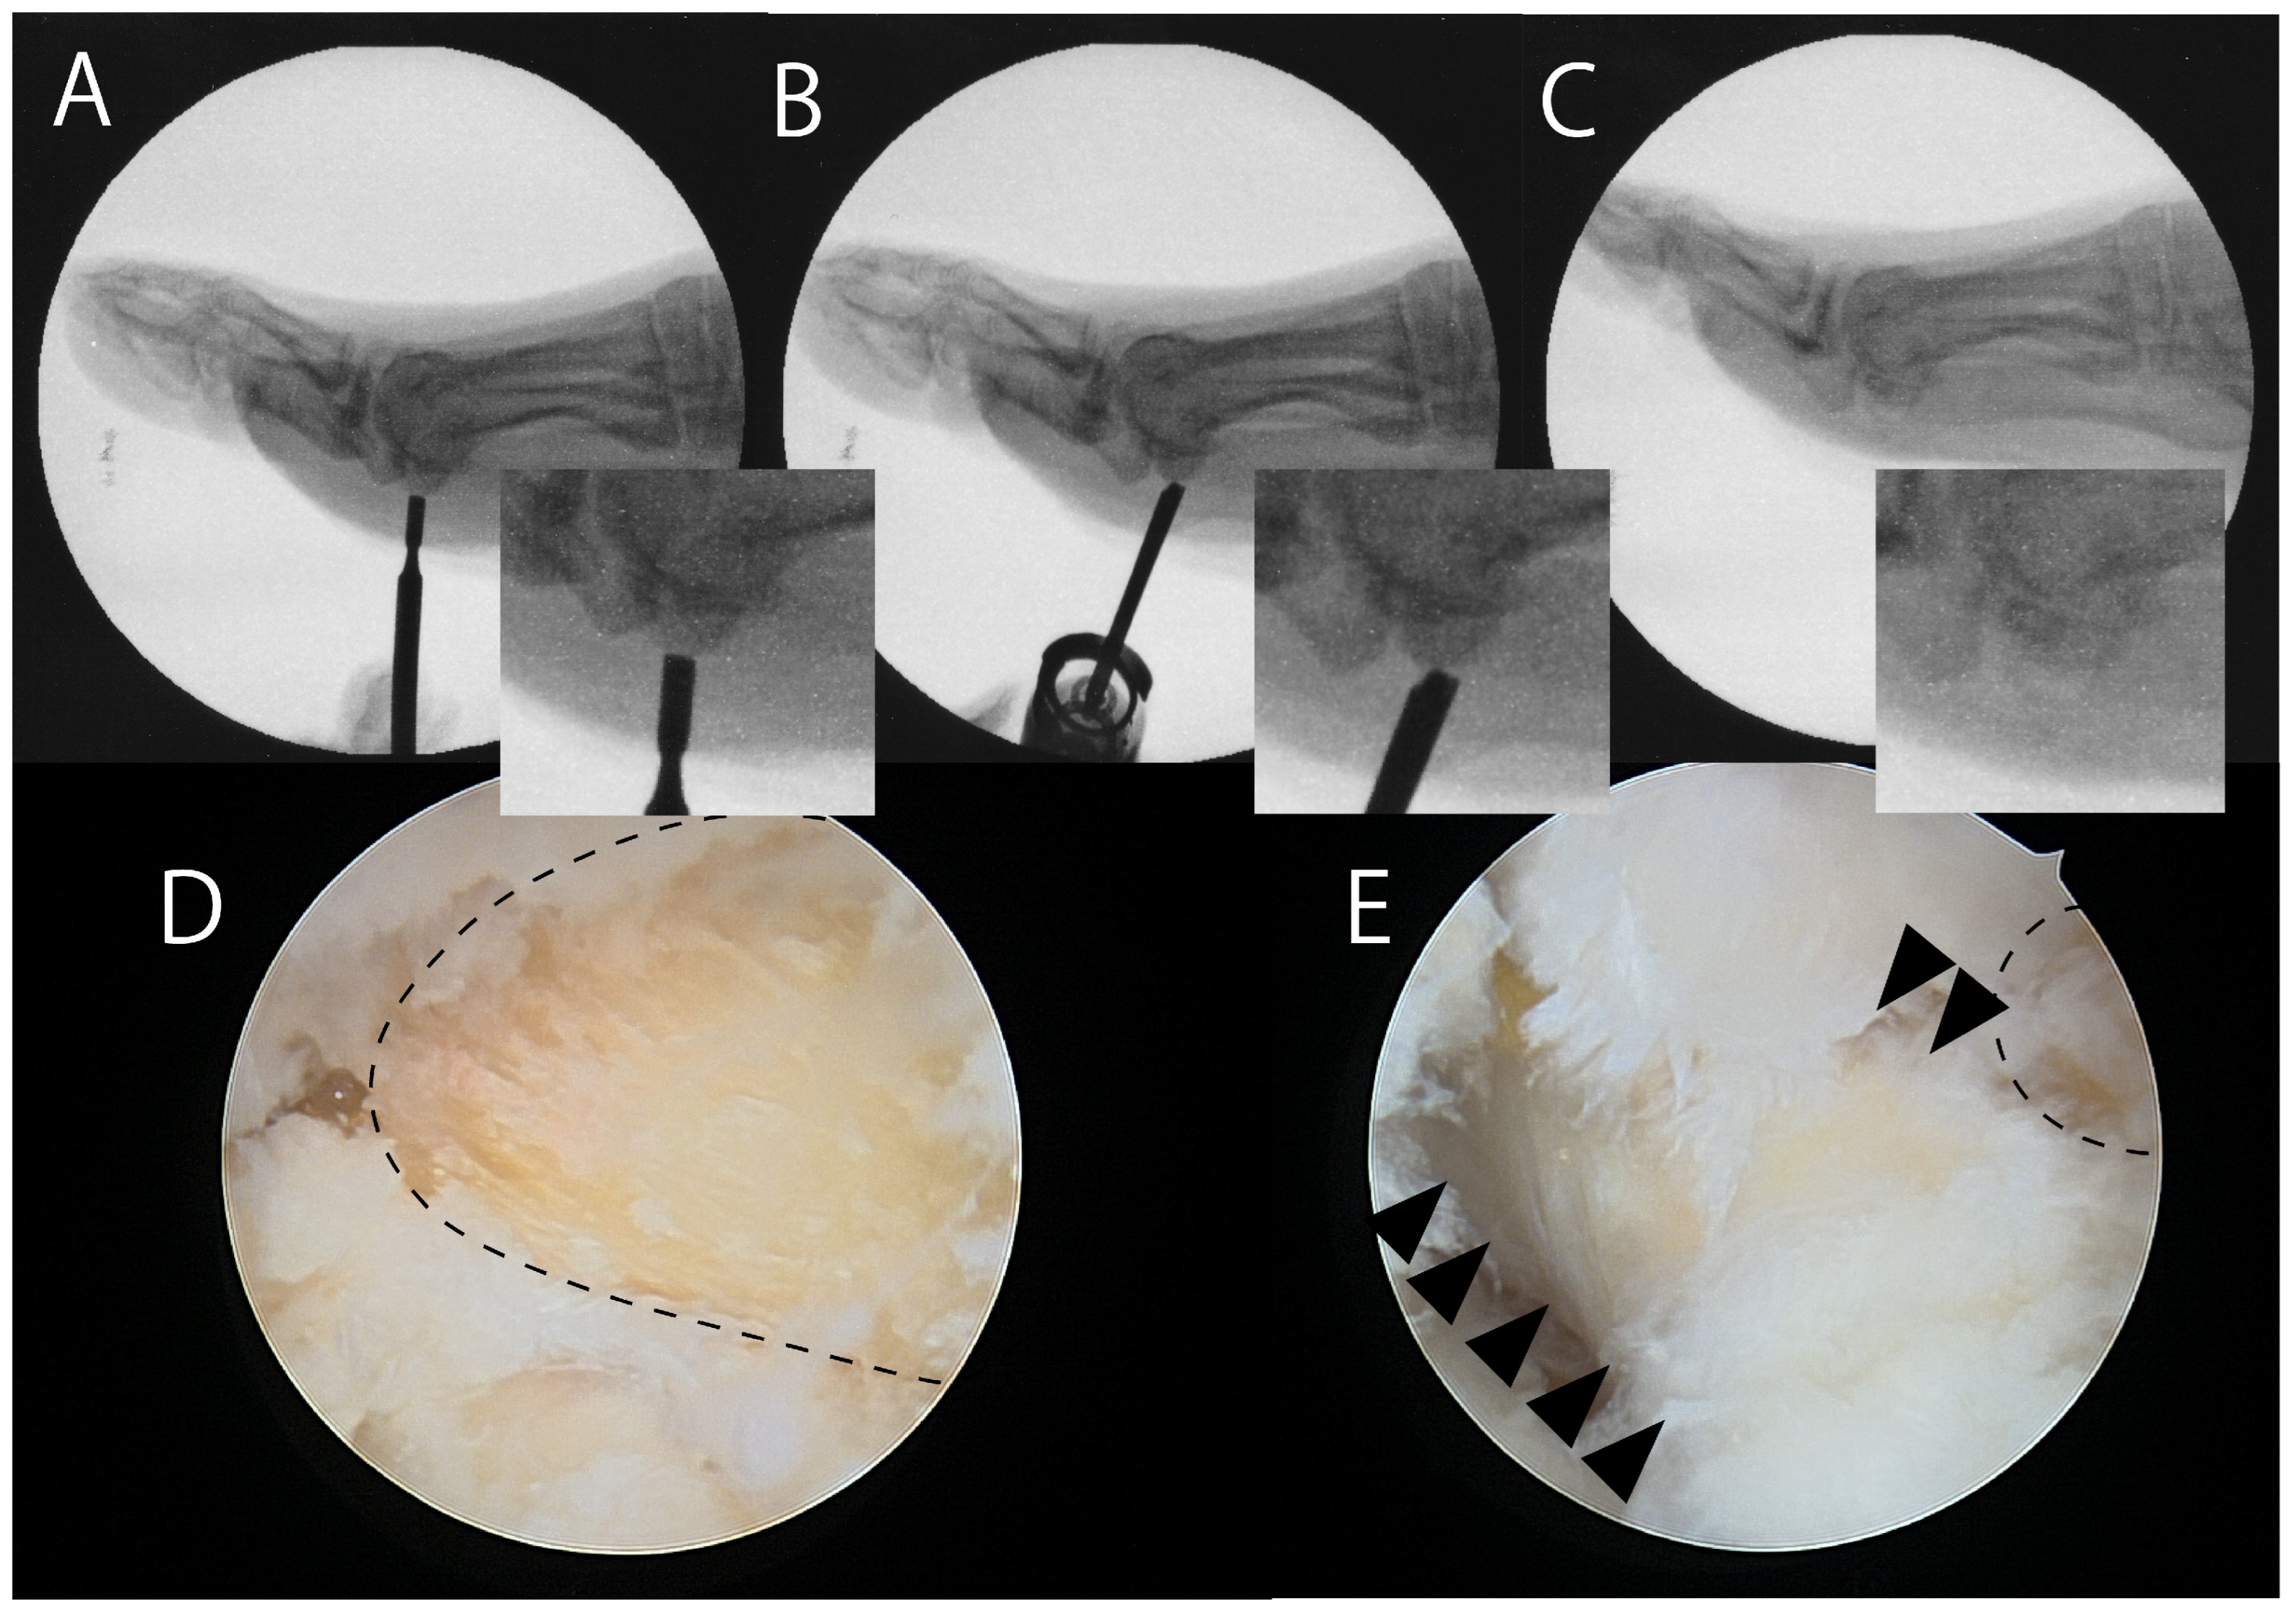

- Nakajima, K. Arthroscopic autologous bone grafting for hallux sesamoid fracture nonunion results in a high rate of complete resolution. Arthrosc. Sports. Med. Rehabil. 1789, 4, e1789–e1797. [Google Scholar] [CrossRef]

| Nakajima (2022) [73] | Case series 11 (10 tibial, 1 fibular) | Arthroscopic bone grafting | VAS 72.0 → 12.0 VAS of 0 and JSSF of 100 observed in 9/11 | Persistent pain (2/11) |